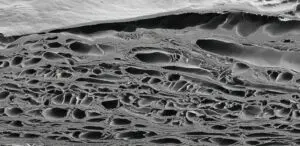

Fish skin is homologous to human skin, with a comparable pore structure that facilitates rapid cellular ingrowth. The gentle EnviroIntact™ process preserves the native extracellular matrix architecture — including the natural arrangement of collagen fibers, elastin, and glycosaminoglycans — creating an ideal scaffold for host cell infiltration and tissue formation.

The intact structure of the fish skin provides a framework to support tissue regeneration. The natural porosity enables rapid ingrowth of fibroblasts (connective tissue) and blood vessels. When grafted onto a wound, human cells migrate into the fish skin pores and start forming connective tissue and facilitating neovascularization. The body incorporates the fish skin within 5–7 days.